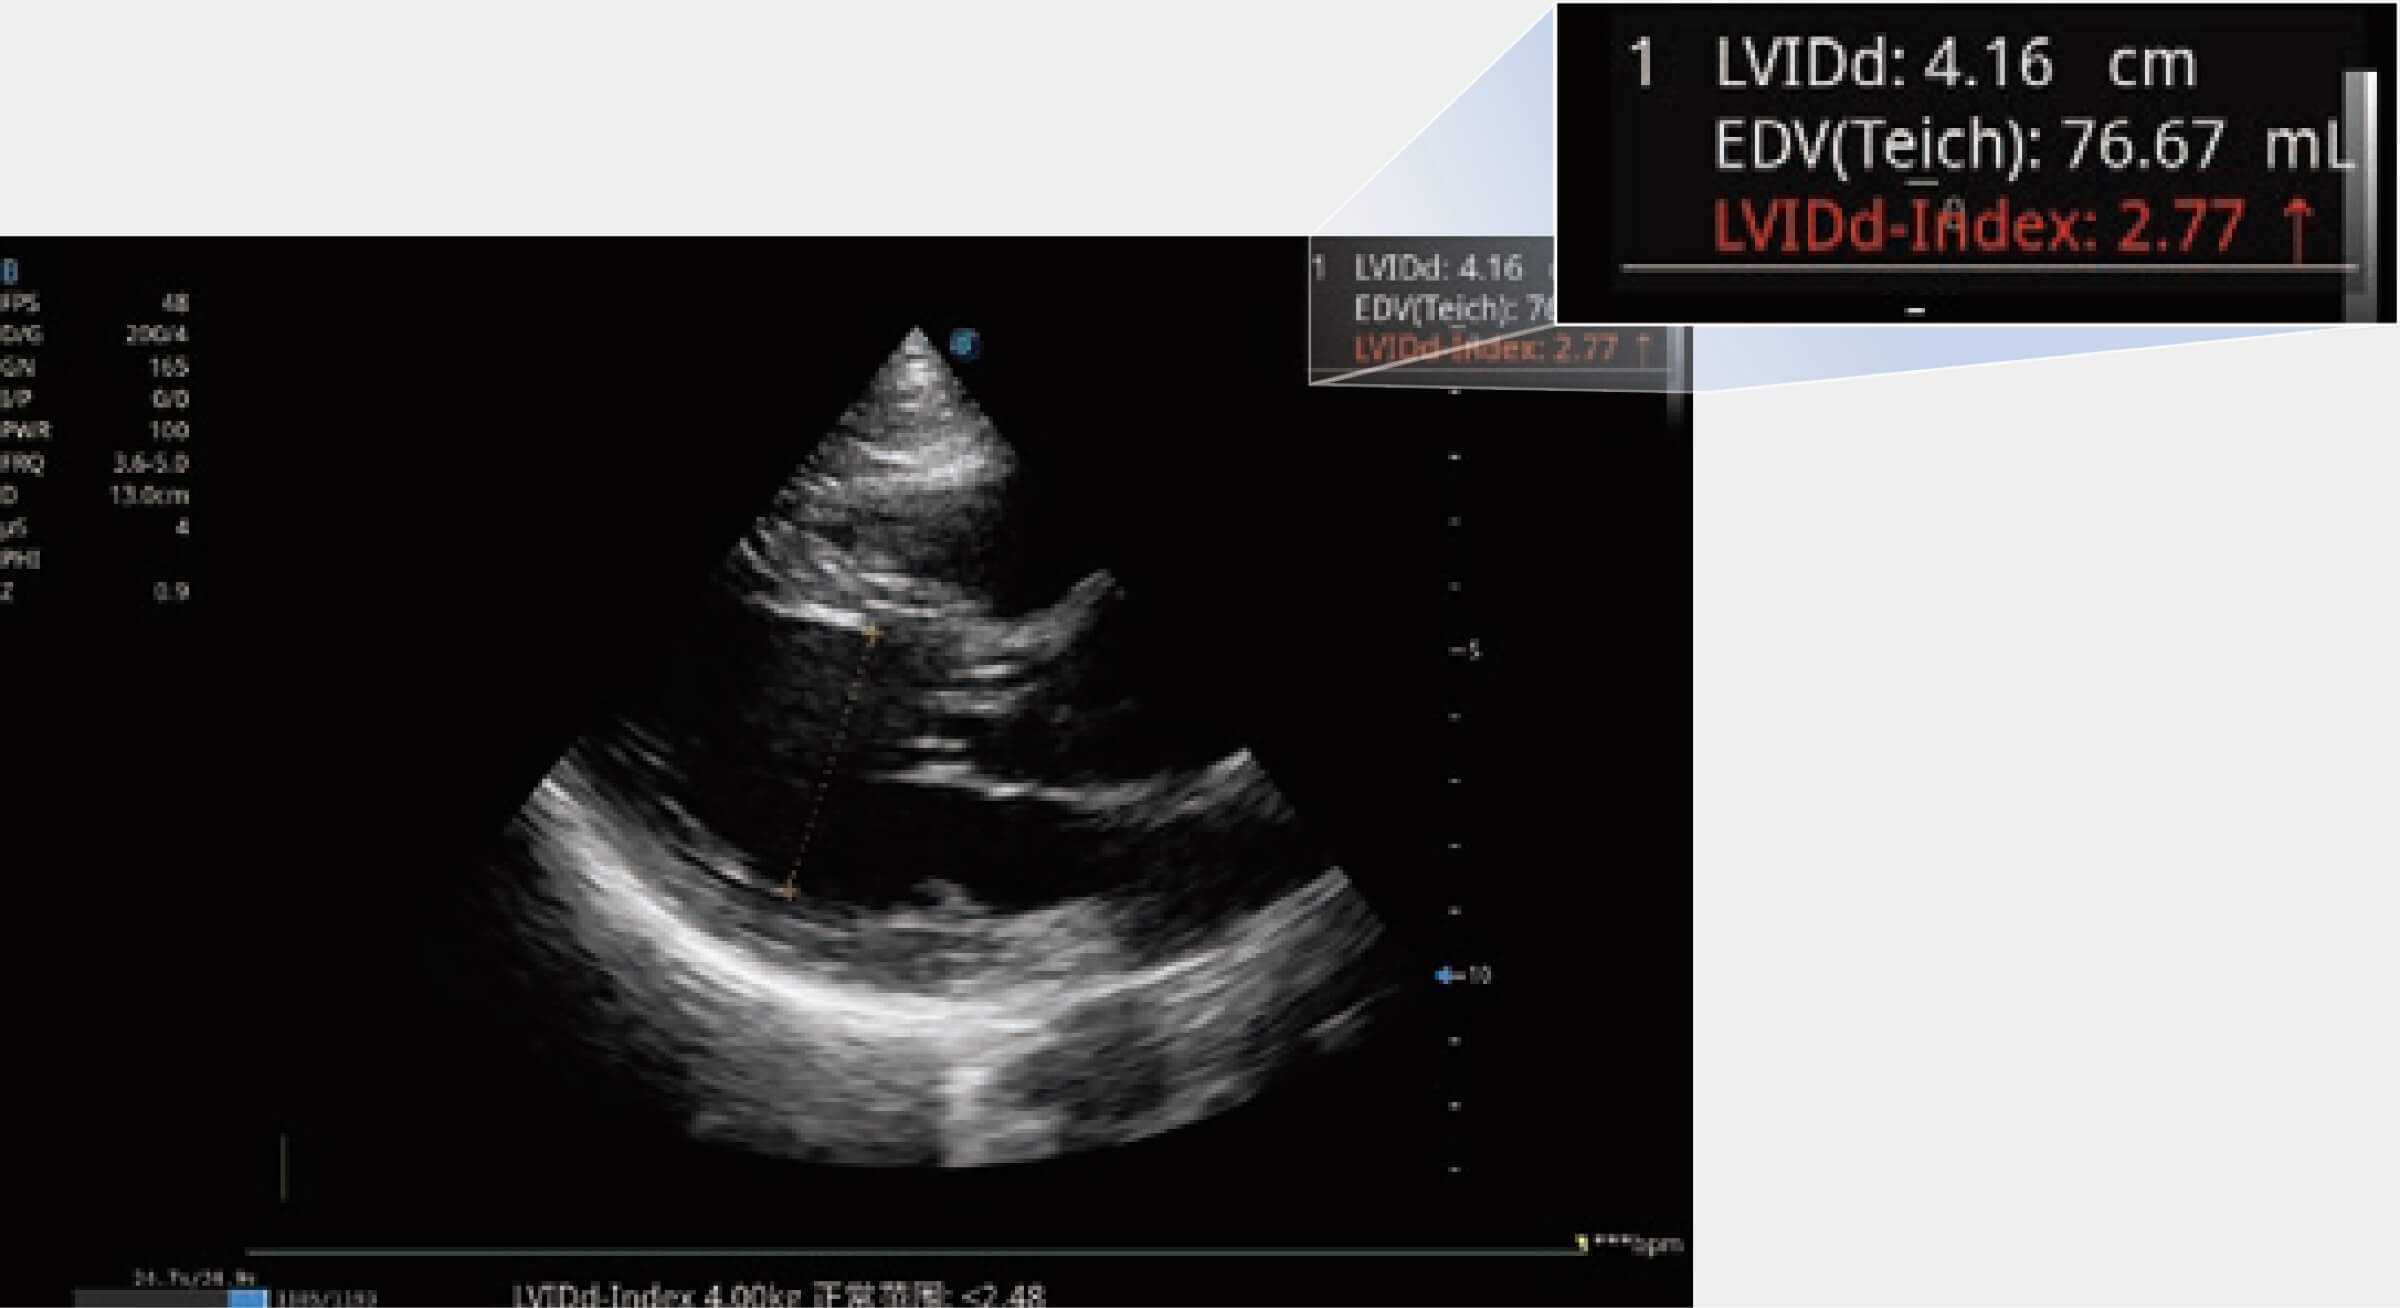

當(dāng)心臟測量結(jié)果超出正常范圍時(shí),可實(shí)時(shí)預(yù)警提示動物醫(yī)生,減少疾病漏診概率。